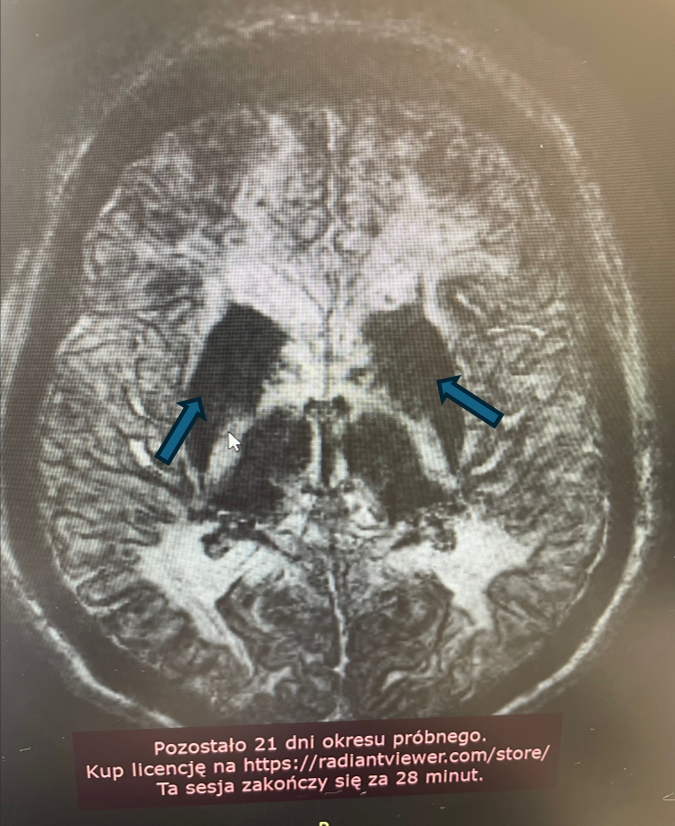

Rycina 1. Cechy akumulacji jonów żelaza w obrębie jąder podkorowych. (T1)

Rycina1